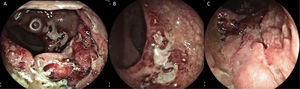

The rectosigmoidoscopy revealed severe inflammatory changes and deep inflammatory ulcers with irregular edges that compromised the middle and distal rectum, with anal canal involvement (Fig. 1A-C). Biopsies were taken to identify the causal agent. Included in the pathology study was abundant lymphoplasmacytic infiltrate of the mucosa, with no viral cytopathic changes, with atrophy, and no dysplasia. Direct testing with techniques for mycobacteria, cytomegalovirus, and fungi was negative, as were the Thayer-Martin agar for Neisseria gonorrhoeae infection and the PCR for fungi and mycobacteria, and so PCR in C. trachomatis tissue was ordered. The VDRL serologic test for syphilis was reactive at 16 dilutions. Thus, in addition to treatment with 100 mg, every 12 h, of oral doxycycline, 2.4 million units of benzathine penicillin was administered weekly for 3 weeks.

A) Rectosigmoidoscopy showing the severe inflammatory changes on the first and second Houston’s valves: marked edema, erythema, and deep, fibrin-covered ulcer. B) Severe inflammatory involvement in the distal rectum, with obvious edema and mucosal thickening. C) Deformity and deep ulcer at the level of the distal rectum, with irregular edges and a sharply demarcated aspect, with anal canal involvement.